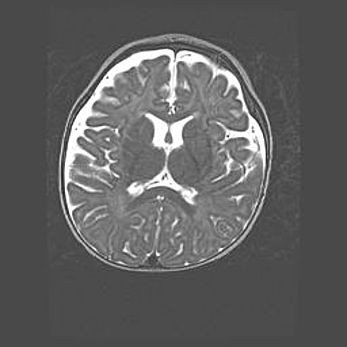

Сообщающаяся гидроцефалия. Кистозная энцефаломаляция головного мозга.

Возраст: 3 месяца 4 дня

Вес: 3100 г

Пол: женский

Окружность головы: 34 см

Срок гестации: 31 неделя

Кистозная энцефаломаляция головного мозга - одна из форм поражения головного мозга в детском возрасте. Характеризуется возникновением множественных и распространённых кист в коре, белом веществе и подкорковых образованиях головного мозга у плодов, новорождённых и детей раннего возраста. Развитие кистозной энцефаломаляции связано с внутриутробной асфиксией и гипотонией, родовой травмой, тромбозом синусов, пороками развития сосудов, инфекциями, сепсисом и другими причинами. Наиболее значимые инфекционные агенты: вирусы простого герпеса, цитомегалии, краснухи, токсоплазмы, энтеробактерии, золотистый стафилококк и другие.